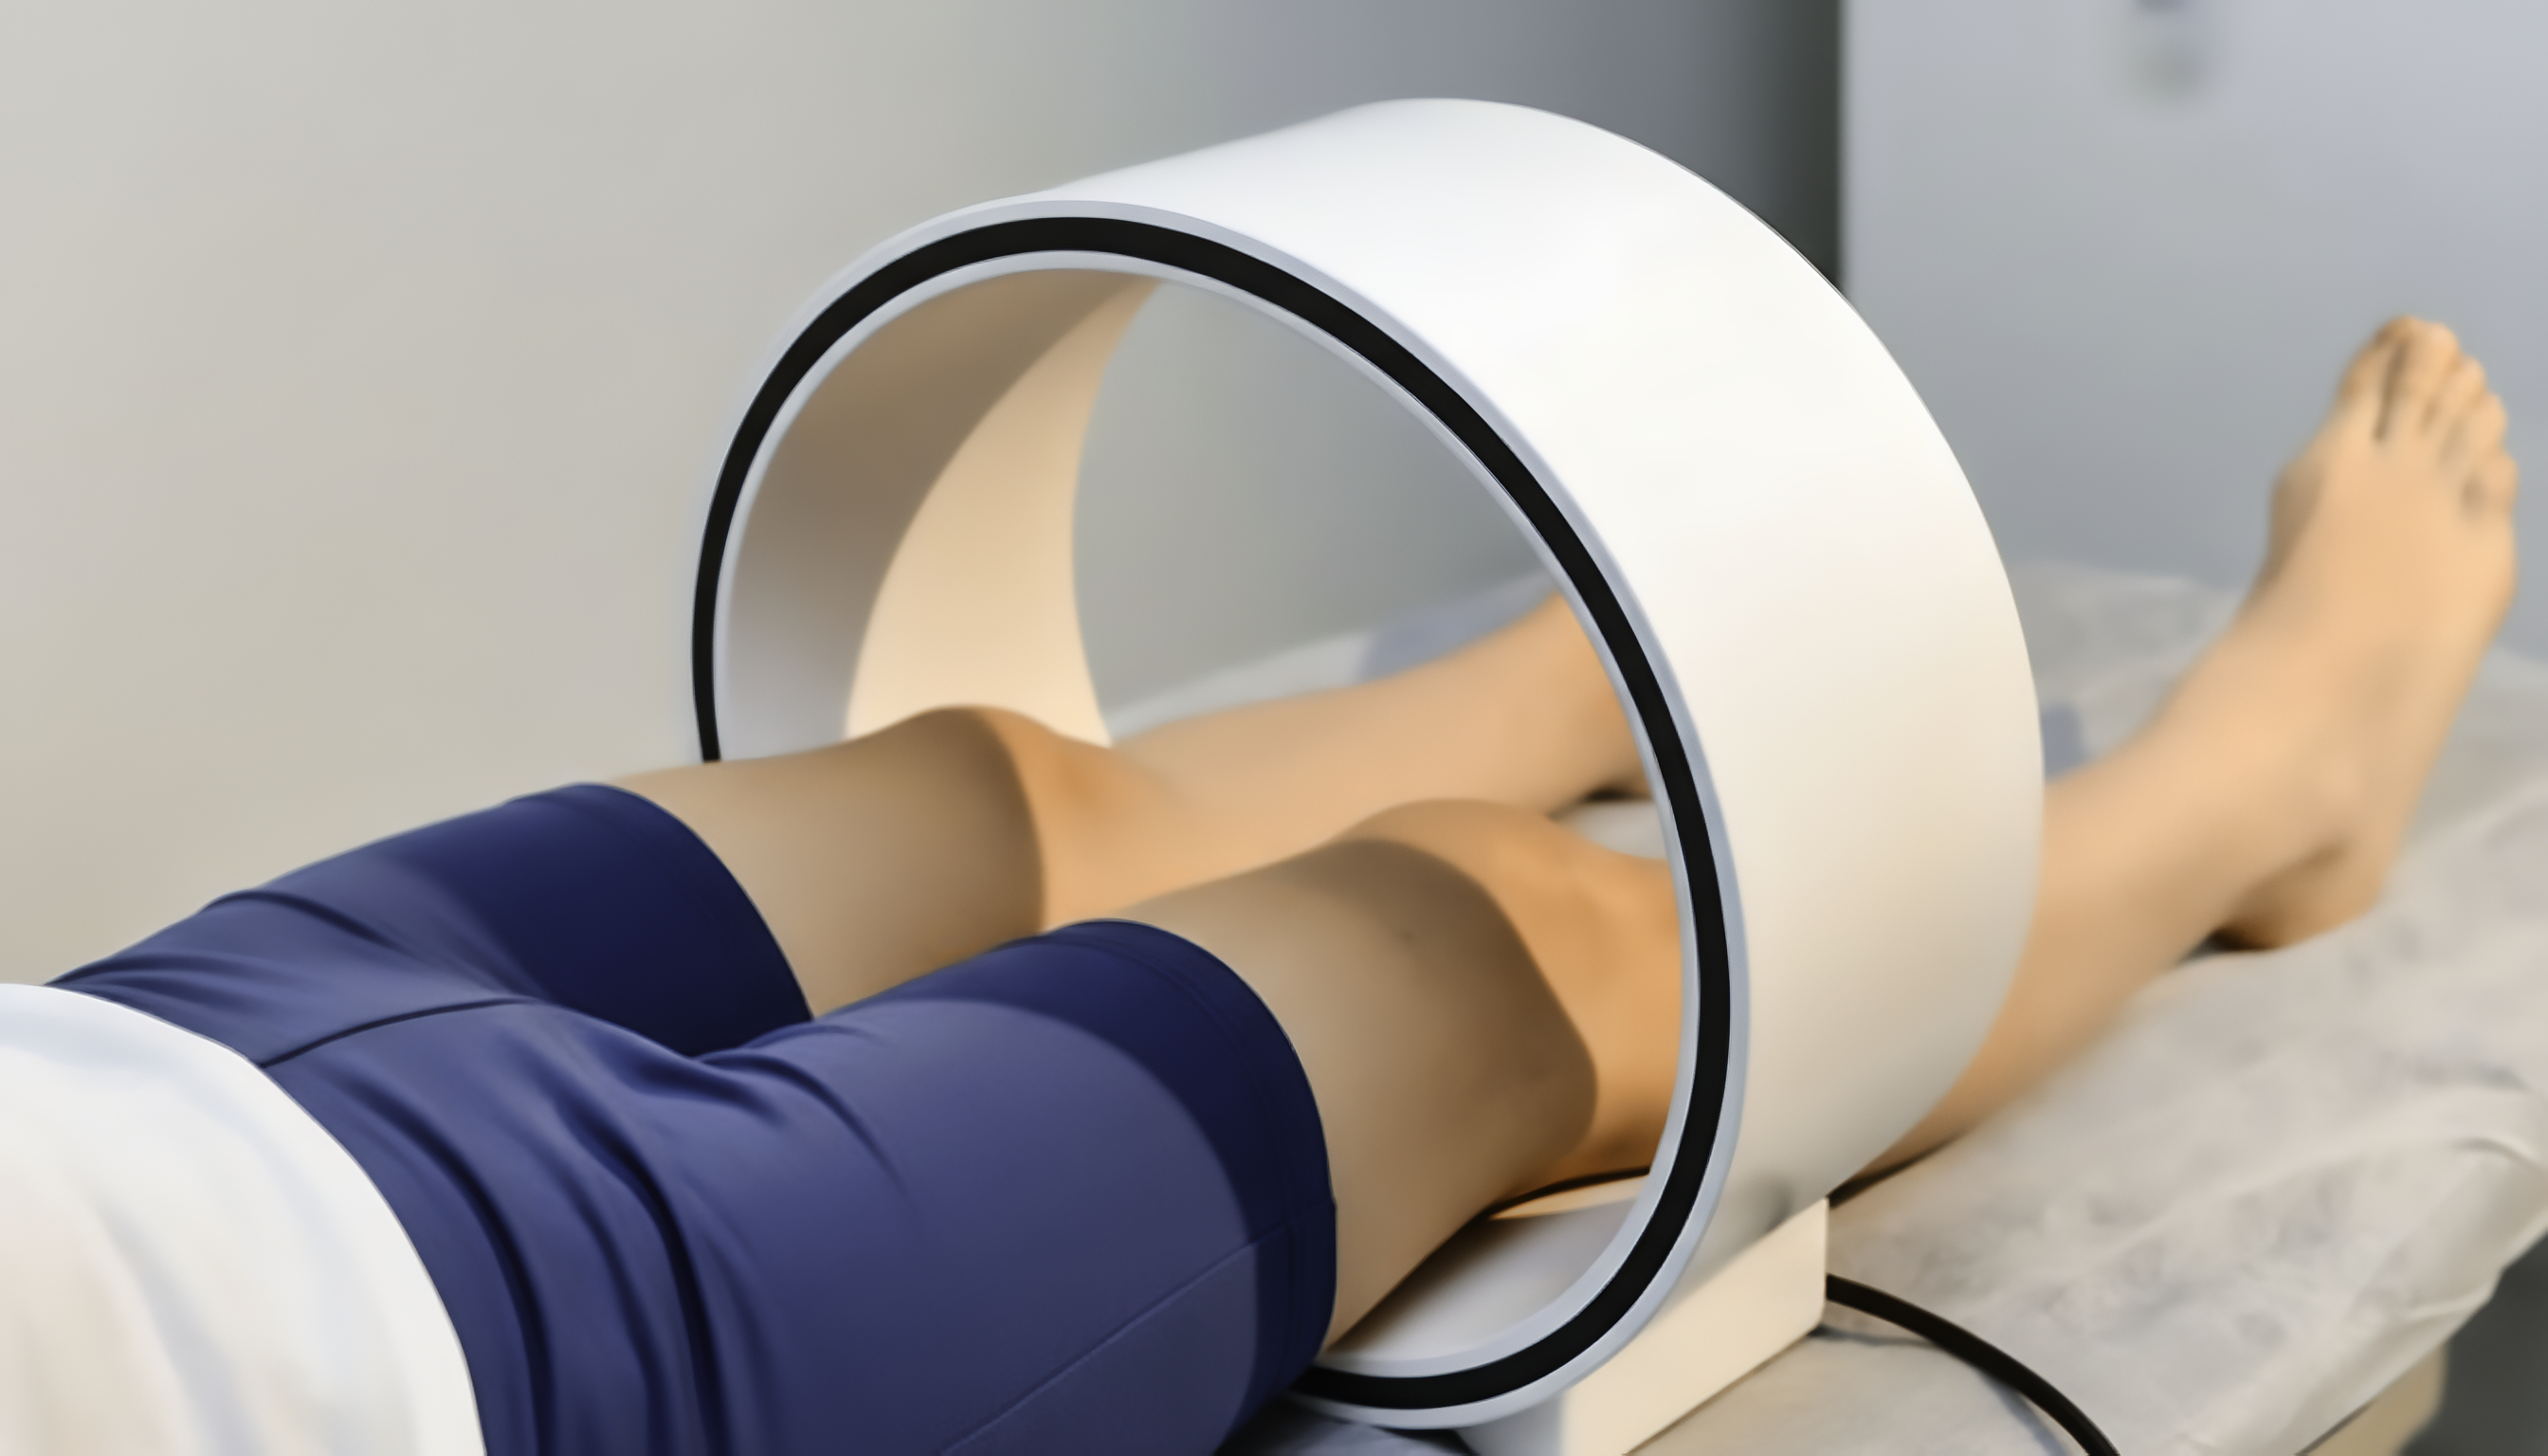

REHABILITACIÓN

Y FISIOTERPIA

Tu bienestar, en manos especializadas

Manguito Rotador

Hernia Discal

Nervio Ciático

Espolón Calcáneo

Cervicalgia

FISIOTERAPIA DEPORTIVA

FISIOTERAPIA GERIÁTRICA

Fortalecimiento Muscular

Movilización Articular

Rehabilitación Postquirúrgica

FISIOTERAPIA NEUROLÓGICA